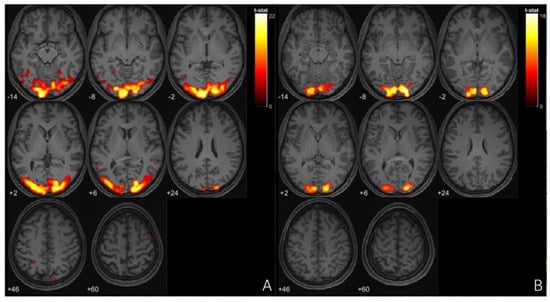

Functional MRI (fMRI) studies of migraine with aura (MA) have identified distinct neural alterations, particularly in resting-state functional connectivity (rs-FC). Increased rs-FC is observed in regions such as the occipital cortex, sensorimotor networks, and visual areas like the lingual gyrus, which play a critical role during both ictal and interictal phases of MA [97,98], [Figure 3 and Figure 4]. Altered connectivity is also found in the thalamus, insula, and cingulate cortex, suggesting the involvement of key pain-processing networks [99]. Furthermore, differences in rs-FC between MA and migraine without aura (MwoA) point to potential biomarkers distinguishing these subtypes [100]. These findings support the notion that distinct neural circuits may underlie the different clinical presentations of migraine, offering new insights into the pathophysiology of the disorder. In tension-type headache (TTH), fMRI studies highlight distinct neural changes that may offer insight into the underlying mechanisms of the condition. Increased fractional amplitude of low-frequency fluctuations (fALFF) is observed in the right posterior and anterior insula in episodic TTH patients compared to healthy controls, while reduced fALFF is found in the posterior cingulate cortex [101]. ReHo analysis reveals increased activity in the right medial superior frontal gyrus [102], though other studies report decreased ReHo in regions such as the bilateral caudate nucleus and frontal gyri [103]. These findings suggest a disrupted balance of activity across key pain and sensory processing regions, providing a better understanding of TTH’s neural basis and potential therapeutic targets. In trigeminal autonomic cephalalgia (TAC), including cluster headache (CH), fMRI studies have documented altered functional connectivity and brain activation patterns. In CH, increased rs-FC is noted between the hypothalamus and regions such as the pregenual anterior cingulate cortex, visual cortex, thalamus, and right insula [104]. Decreased FC is observed in the right frontal pole and right amygdala in chronic CH patients [105]. These altered connectivity patterns suggest that disruptions in both the sensory and emotional processing circuits contribute to the intensity of pain in CH. Additionally, TAC subtypes like short-lasting unilateral neuralgiform headache attacks with conjunctival injection and tearing (SUNCT) exhibit activation in the posterior hypothalamus, brainstem, and frontal cortices during attacks [106,107,108]. This indicates a significant involvement of the hypothalamus and brainstem in the pathophysiology of TAC. In the case of other primary headaches, such as new daily persistent headache (NDPH), fMRI studies have shown abnormal functional connectivity in brain regions involved in emotion and pain regulation [109]. These abnormalities suggest that NDPH may involve disrupted integration between pain processing and emotional regulation networks. Additionally, structural changes, including alterations in cortical area and grey matter volume, have been reported in NDPH patients [110]. These structural findings further emphasize the chronic nature of NDPH and its potential link to persistent alterations in brain structure and function. These findings underscore the complex neural mechanisms underlying these various headache disorders, suggesting that personalized treatment strategies targeting these neural alterations may hold promise for more effective management.

Figure 3. (A) fMRl imaging of occipital cortex of patient with migraine during aura episode, cluster size- 8068voxels, (B) fMRl imaging of occipital cortex of patient with tension type headaches, cluster size- 2595 voxels.